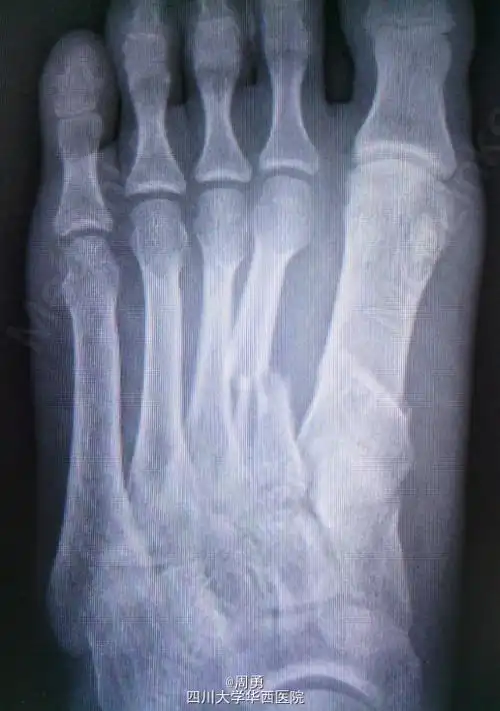

跖骨骨折

第一跖骨陈旧性骨折畸形愈合

右脚第一跖骨基底部骨折日志右脚lisfranc损伤

你好,麻烦请问一下我的右脚,2,3,4跖骨远端粉碎骨折.

左足第1,2跖骨中近1/3骨折闭合复位克氏针内固定术

一个罕见的跖骨骨折